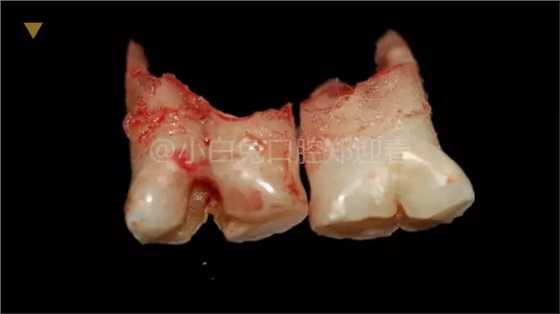

患兒,10歲,因上前牙未替換來(lái)診,查體:輕度反合,51和52、61和62均融合,且存在間隙約4mm,全面曲面斷層片顯示:11、21未萌,52、51、61、62牙根均有不同程度的生理性吸收。

拔出后的離體牙